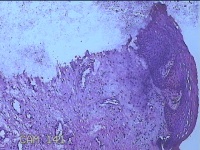

宫颈组织

性别

女

年龄

54岁

临床诊断

宫颈上皮内瘤变Ⅰ级

一般病史

反复阴道脱出肿物3年余。

标本名称

大体所见

灰白暗红色组织4.8x1.5x0.3cm一块,肥大,糜烂,切面灰白粉红色,质软

图3